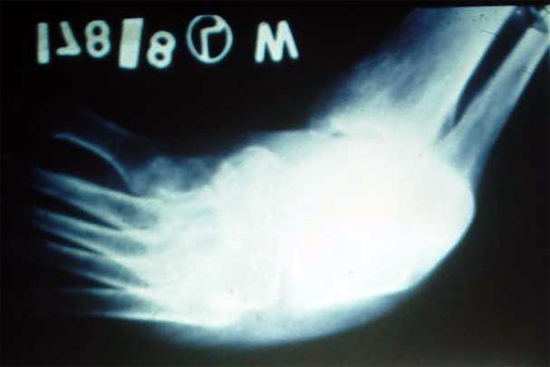

TEV

Gulam Rasul